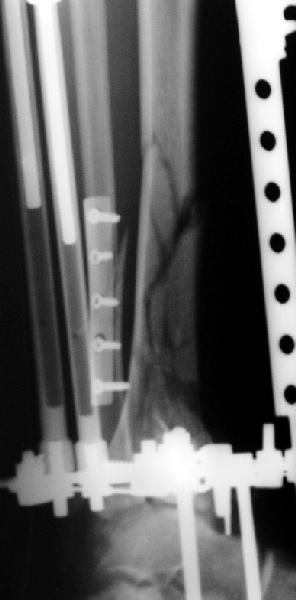

Мне кажется, что все дискутирующие согласным с одним - надо воостанавливать в данной ситуации суставную поверхность. Сделать это закрыто (когда суставная поверхность состит из 3-фрагментов)лично для меня не реально. Конечно можно открыто отрепонировать, зафиксировать спицами и оставить в аппарате, но роль аппарата и выполняет LSP. Разрез в области внутренней поверхность голеностопного сустава и небольшой разрез в ср/3 голени для проксимальных винтов, надкостница не обдирается, пластина вводится подкожно.

Вид конечности на следующий день после операции.

Пластинка красивая. Чуть только спереди назад идет, не сосем по оси большеберцовой кости. А там не маловато фиксаторов собственно в дистальном суставном конце кости? А вправляли его как? Как будто или осталось запрокидывание кзади или недонизведен передний край. Но с учетом исходного тяжелейшего повреждения - все равно здорово.